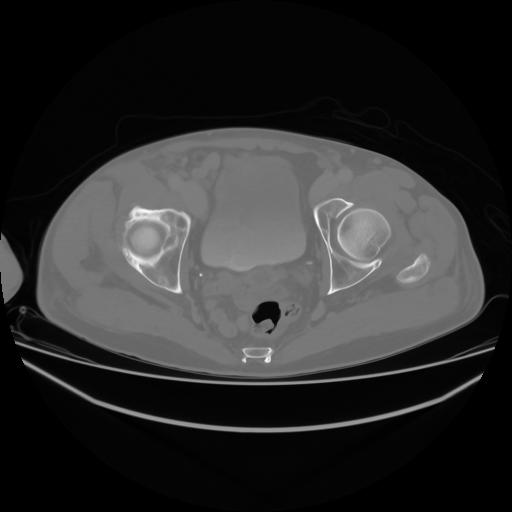

4 CUERPO,CE,Axial,3.0,CUERPO,,